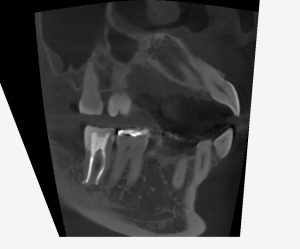

レントゲンを見てみよう。

(術前のレントゲン、CT)

半埋伏智歯(半分歯茎の中に埋まっている親知らず)の影響で、右下7番の遠心にう蝕があったであろうことが分かる。

この場所は、親知らずが無ければ、本来虫歯ができるはずがない場所だ。

このようなことがあるので、半埋伏智歯は早めに抜いておいた方が良いのかもしれない。

一つ言えることは、この場所に虫歯ができると「治療が非常に難しくなる」ということである。

理由は簡単、見えにくいからだ。

現に過去の虫歯治療の状態は、問題だらけだ。

・虫歯も取りきれていない

・裏層したセメントは大きくはみ出している

・修復物の適合も全くあっていない

見えない場所を、盲目的に、感覚頼りに治療したのだろう。

そして、結果的に神経が死んでしまい、かなり広範囲に骨が溶けてしまっている。